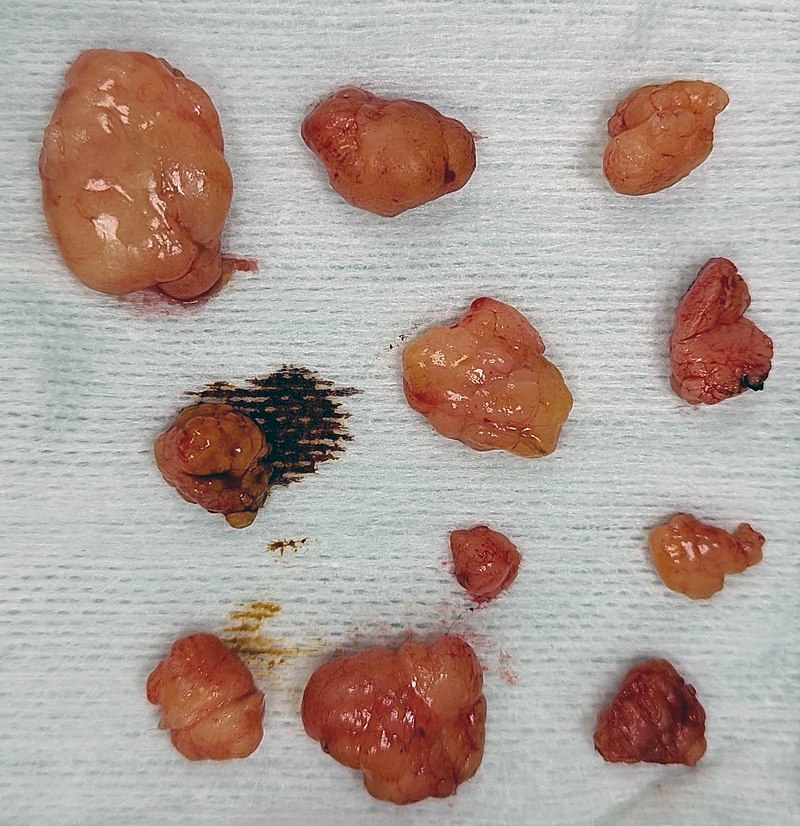

Lipomas may be treated by surgical excision.

Treatment of liposarcomas involves surgical excision.